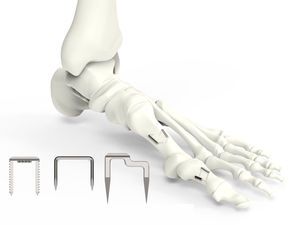

U-Klammer aus Titan wird zur Fixierung des Weichgewebes am Knochen bei der ACL-Rekonstruktion verwendet.

... Das VA-LOC™ Platten- und Schraubensystem aus expandierbarem Edelstahl ist ein äußerst vielseitiges Implantat für Osteotomien und Arthrodesen am Fuß. Es eignet sich besonders für Arthrodesen des Kalkaneus-Kubuskopfes, des Talonavikulargelenkes ...

Orthopädische Klammer / für Vorderfuß-Osteotomie54.030 series

... Kleine Größe 12x12x18 mm Mittlere Größe 15x15x22 mm Großes Modell 25x18x32 mm Modifizierte Heftklammer 15x15x22 mm ...

Die EasyClip-Klammern sind indiziert für Hand- und Fußknochensegmente, für die Osteotomie-Fixierung und für die Gelenkarthrodese.

... Fußextremitäten - Seitliche Zähne bieten eine hervorragende Verankerung im Knochen Einfach zu verwendendes Instrumentarium: Führungsschablonen ermöglichen die korrekte Platzierung der Wölbungen Der Kompressor ist in der Lage, die Knochenfragmente ...